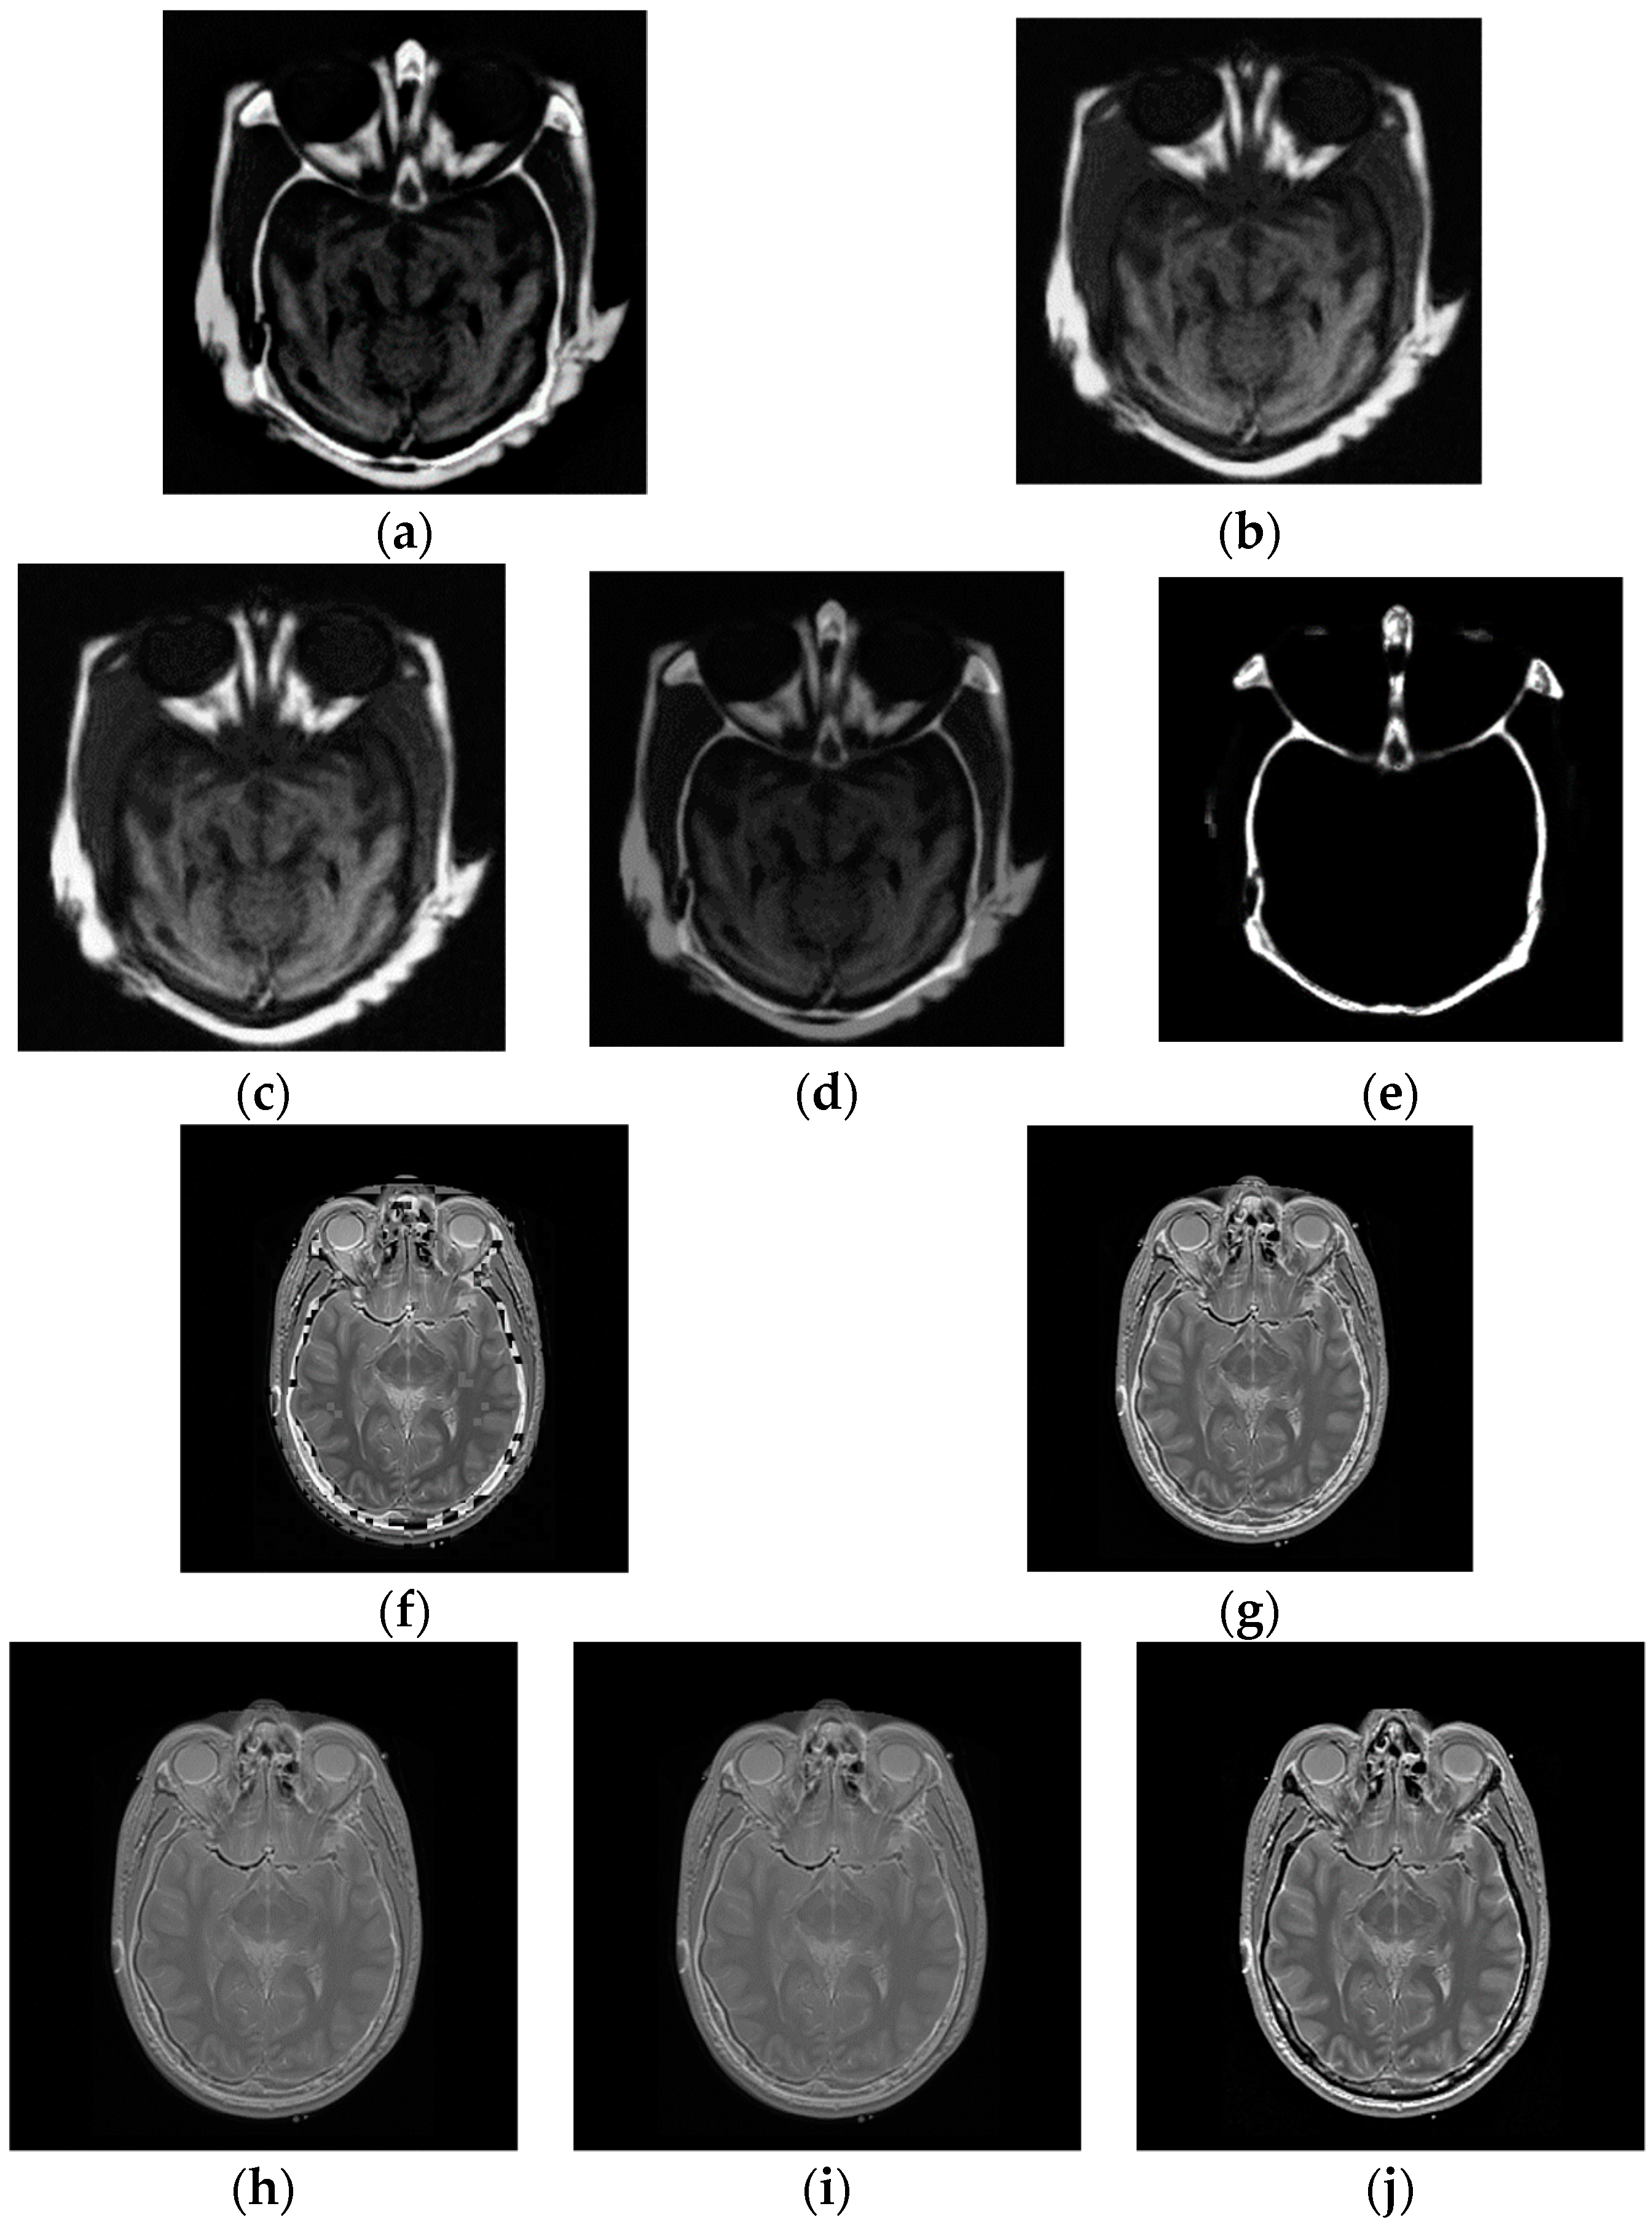

4.3. Multi-Modal Image Fusion

In multi-modal tests, the original images shown in Figure 2 are applied to generate the fused images. The fusion experiments are performed on these images using CP, PCA, DCT, LP and the average methods, and the corresponding fused results, displayed in Figure 6a–e, show the fused results for two original images in Figure 2a using five algorithms, together with Figure 6f–j giving the fused images of the two input images shown in Figure 2b.

The final fused images should both include the information of the two original images. Nonetheless, in the first test of the multi-focus images, the fused image in Figure 6e by CP fusion algorithm almost only consists of the information of the CT image and hardly includes the information of the MR image. The fused results obtained by PCA and DCT are similar, and only provide the information of the MR image instead of the CT image. The LP fusion method illustrates the information of the CT image and also displays the MR information. Likewise, for the fusion experiments of the two original images given in Figure 2b, the fused image acquired via the CP algorithm only exhibits the MR information and does not obtain the information from the CT image.

Similarly to section B, to validate the performance of our proposed metric in the fusion of multi-modal images, Table 4 and Table 5 depict the metric values between the fused images and original multi-focus images sketched in Figure 2a,b calculated by mutual information, NMI, the Petrovic measure, Tsallis divergence and the proposed method, respectively.

It is observed from Table 4 and Table 5 that the proposed metric can provide the consistency evaluation order for two groups of multi-modal image fusion adopting five fusion algorithms, which is the same as the subjective rank. However, the evaluated results of the MI, NMI, Tsallis divergence and Petrovic metric do not correlate with the subjective test. The experimental results demonstrate that the presented metric is an effective evaluation measure for the fusion performance of multi-modal images.